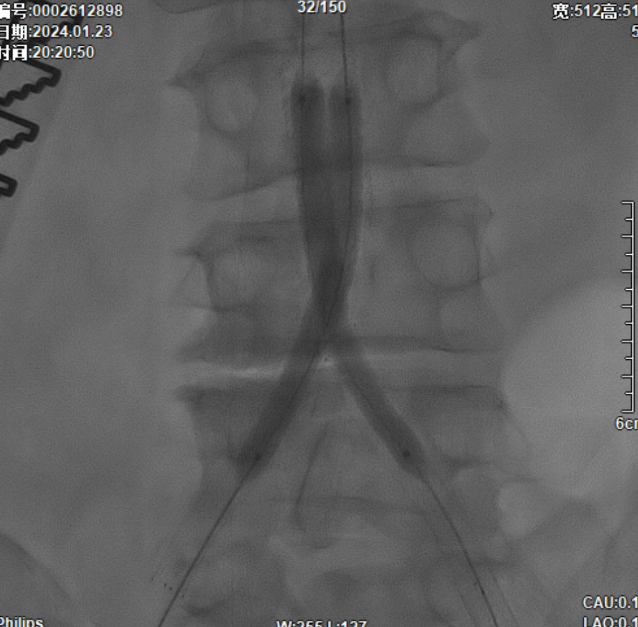

髂动脉重建

该图解释为何远端距离双侧髂总动脉分叉至少1.5cm,以避免后扩张时大球囊对髂动脉造成损伤。

CERAB技术的关键点一:经双侧股总动脉植入2枚VBX球囊扩张式覆膜支架(8L×79mm),与腹主动脉覆膜支架腔内平行放置,且两枚支架端平齐对接。

CERAB技术关键点二:先用14mm×40mm球囊分别扩张双侧髂肢的腹主动脉段。

再用8mm球囊对双侧髂支腹主动脉段行对吻扩张,以确保双侧髂支与腹主动脉覆膜支架腔内获得良好的贴壁形态,最大程度减少空腔,降低远期再狭窄发生率。